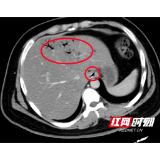

CT显示,肝脏血管内有明显积气(红圈内)。

进入急诊三科抢救室时,小刘已经神志浅昏迷,呼吸急促,脉搏高达145次/分,血压低至休克,快速血糖检测高到“爆表”,只得抽血测血糖,结果显示为123.10mmol/L,超出正常值20多倍!此外,感染指标明显升高;腹部CT显示:左肝静脉、门静脉、肠系膜静脉及小肠壁积气明显,考虑小肠坏死,随即转入EICU。

“门静脉和肠系膜静脉等出现积气是因为产气细菌进入血液,这种情况在影像学上被称为‘死神之征’,死亡率高达50%”,张兴文表示,小刘由于不良生活方式导致体重超标,并患上糖尿病,在此之前一直没有规范治疗和改变不良生活方式,这次因为肠道菌群失调、移位出现肠源性感染,引发感染性休克,最终导致严重的糖尿病酮症酸中毒(DKA),危及生命。